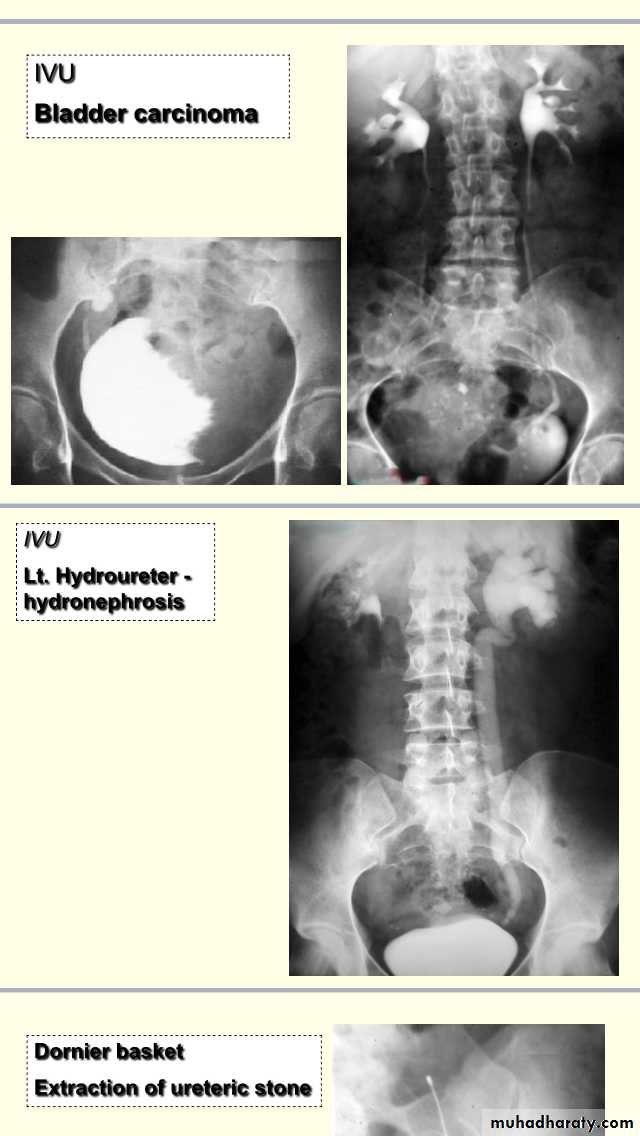

Radiopaque shadow ,smooth ,round surface,(2,5cm)size,solitary.Management of vesical stone:-if no underlying UT pathology ,Rx depend on the size,in pediatric age group by open surgery,in adult:endoscopic Mx,if >3cm cystolithotomy,if 2.5cm endoscopic crushing(cystolithopaxy) or equalIVU cystogram phase :-showing opacity with thickening and irregular of bladder wall(outline) due to neurogenic bladder (multiple saccule in the bladder commonly seen +trabeculation) with diverticulum (paraureteric buldging).

Description:- IVU showing filling defect in the base of bladder ,elevated base,buldging and curvature of bladder extending above symphysis pubis Dx:BPH(median lobe of prostate)